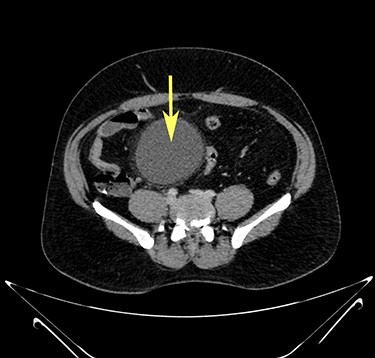

Transverse section image of a contrast-enhanced CT scan of the abdomen at the level 3–3 (Fig. 1), showing a solitary cyst (arrow) with a non-enhancing wall separate from the intestines.